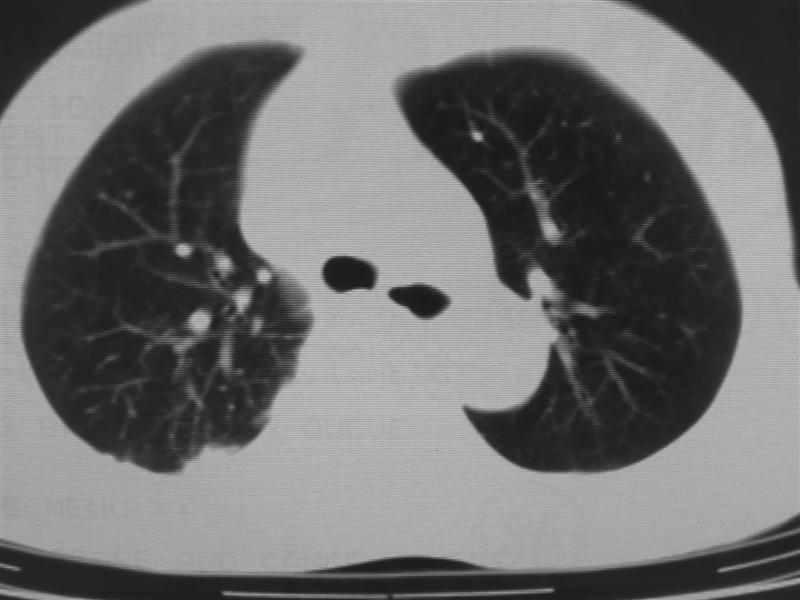

支持右下肺癌伴肺内转移

右下肺周围型肺癌伴双肺右侧叶间 胸膜及右肺门淋巴结转移

考虑肺癌,肺、胸膜转移可能性大。病史一定要尽量完整。

肺癌、肺及胸膜转移可能性大;tb不除外